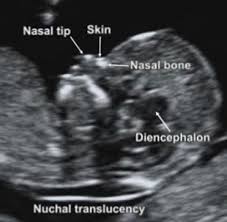

Measurement Of Nuchal Translucency Nt And Other Landmarks Download Scientific Diagram from www.researchgate.net An ultrasound performed on a pregnant woman to help determine the chances that the foetus may develop chromosomal conditions such as down syndrome. Meaning of nuchal scan medical term. The nuchal scan is used in pregnancy to determine if the baby is likely to have a condition such as down's syndrome. As the nt increases, so does the chance of down's syndrome and other chromosomal abnormalities. A nuchal scan or nuchal translucency (nt) scan/procedure is a sonographic prenatal screening scan (ultrasound) to detect cardiovascular abnormalities. The nt scan measures the amount of fluid behind the fetus' neck. Basically, the thicker the nuchal translucency at a given gestational age, the higher the chance of a chromosomal problem. Nuchal scan (plural nuchal scans).

Nuchal scan (plural nuchal scans). All babies have a certain amount of fluid in this area. The nuchal translucency scan or nt scan measures the clear (translucent) space in the tissue at the back of your child's neck. Meaning of nuchal scan medical term. This is a training ultrasound video about nuchal translucency measurements. What do my nt scan results mean? Nuchal translucency and the first trimester combined screening. It describes the correct nt scan technique. The scan is obtained with the fetus in saggital section, and a neutral position of the fetal head (neither hyperflexed nor extended, as it can influence nuchal. In case the nt scan indicates a risk of any abnormality (be it trisomy 13 or 18, or down syndrome), you should know that it doesn't necessarily mean that your baby actually has. Nuchal translucency is a screening test to determine risk of chromosome abnormalities in a fetus. Show declension of nuchal scan. Basically, the thicker the nuchal translucency at a given gestational age, the higher the chance of a chromosomal problem.